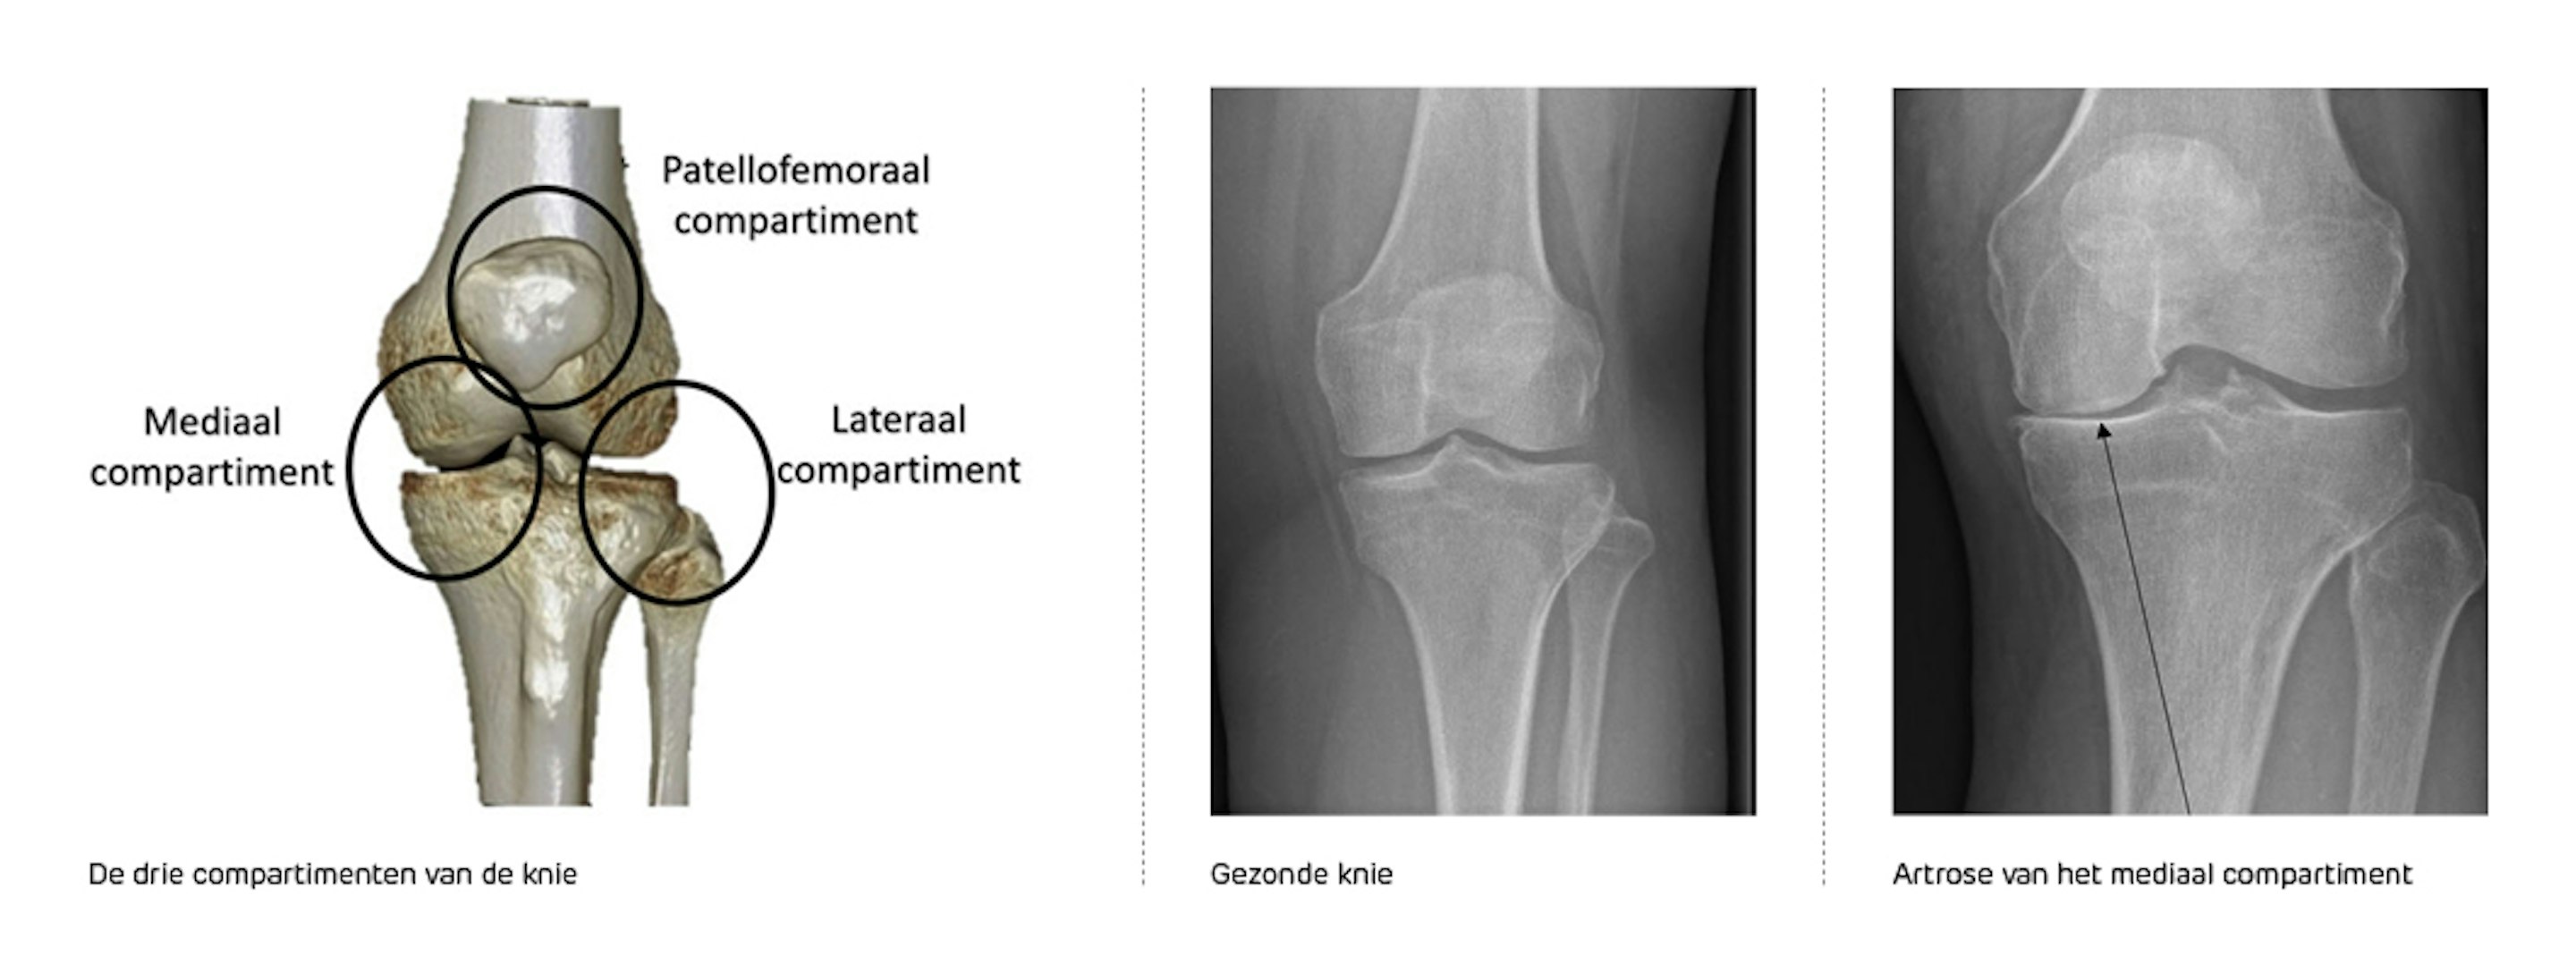

De knie bestaat uit drie delen (gewrichtscompartimenten)

In veel gevallen is er slechts één van de drie compartimenten versleten. Meestal gaat het om het compartiment aan de binnenzijde (mediaal).

We stellen de diagnose op basis van een radiografie. Op onderstaande foto zie je een radiografie van een gezonde knie en van een knie met een duidelijke gewrichtsvernauwing van het binnenste (mediale) compartiment. Er is bot-op-bot contact. Enkel het binnenste (mediale) compartiment is aangetast. Ter hoogte van het buitenste kniecompartiment is er geen artrose te zien.